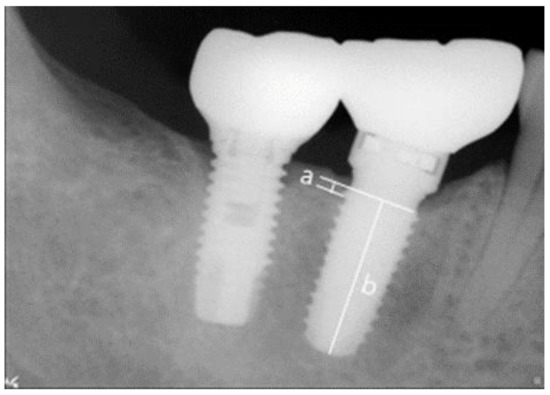

Abutments were connected and, during periodic observations, digital intraoral radiographs were taken by using the parallel technique to evaluate surrounding bone resorption. After setting implant prostheses, mesial and distal bone levels were measured based on fixture-abutment junctions and vertical bone resorptions measured at 6 and 12 months after prosthesis placement were compared and analyzed. Radiographs were taken by using a Portable X-ray unit (Port II, Genoray, Seongnam, Korea) and measurements were obtained by using the PACS software (Digi-X, Hanjin Digi-X Co., Seoul, Korea). The means and standard deviations were calculated after scale correction based on known fixture lengths (Figure 4) [29,35].

Figure 4. References used to measure actual marginal bone resorptions. (a) Marginal bone resorption and (b) implant fixture length.